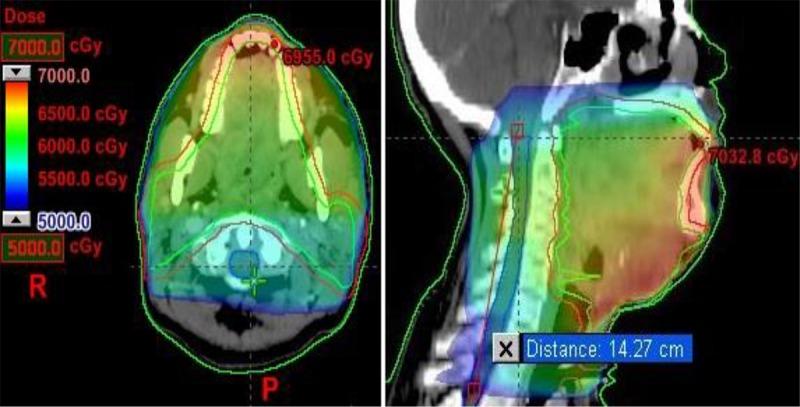

In this analytical study, sixty patients who received more than 50 Gray (Gy) dose for more than 10 cm length of spinal cord participated in the study. All the patients were clinically examined and magnetic resonance imaging (MRI) was performed for patients who had demyelination symptoms. Adequate medical management was provided for all the patients having demyelination.

Demyelination may occur if long segment spinal cord receives dose more than tolerance limit. However target dose should not be compromised up to 54 Gy to spinal cord.

在这项分析性研究中,60例脊髓长度超过10厘米且接受超过50格雷(Gy)剂量放疗的患者参与了研究。对所有患者进行了临床检查,对有脱髓鞘症状的患者进行了磁共振成像(MRI)检查。为所有有脱髓鞘的患者提供了适当的医疗处理。

如果长节段脊髓接受的剂量超过耐受极限,可能会发生脱髓鞘。然而,脊髓的靶剂量在54 Gy以内不应受到影响。